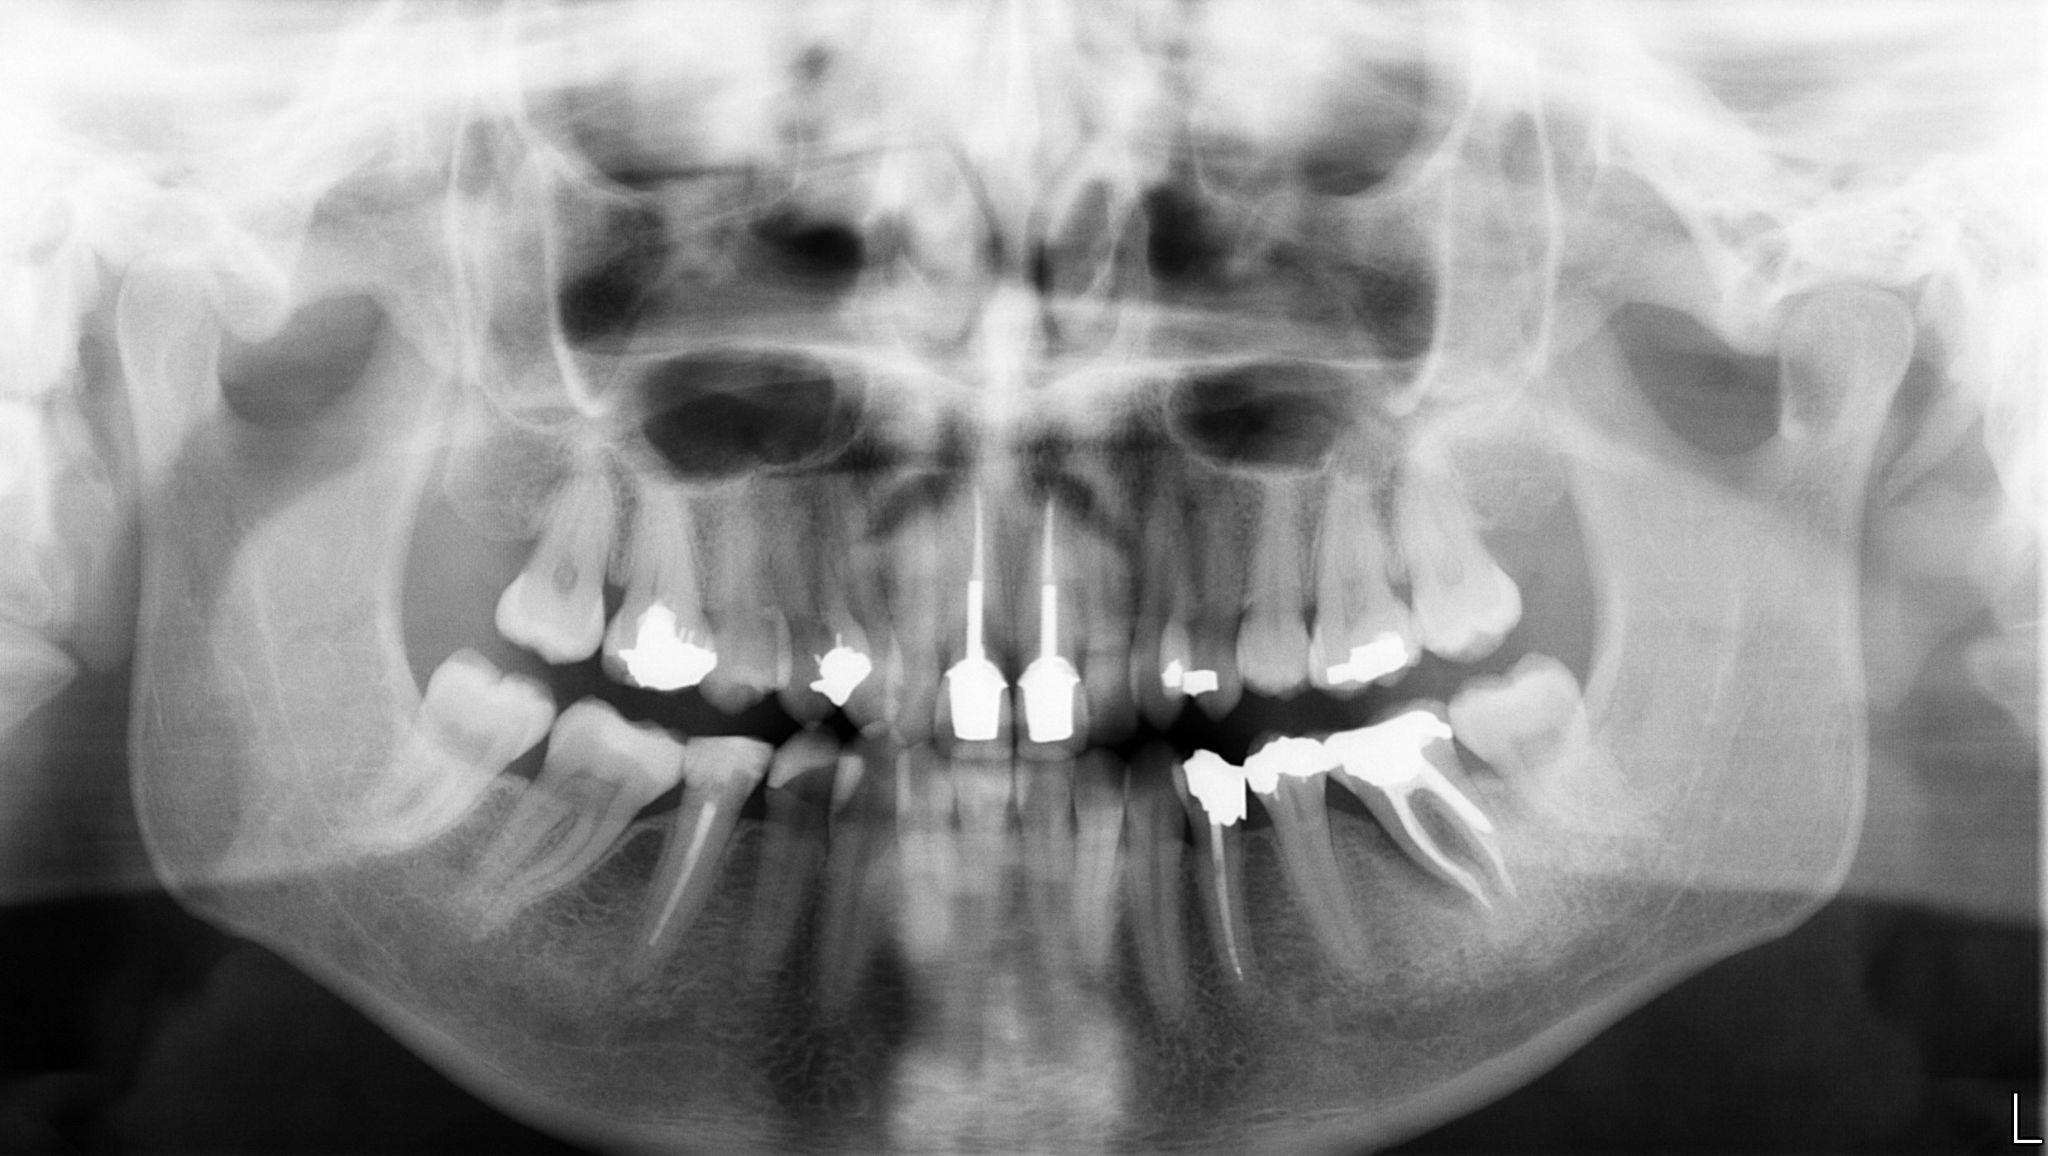

1. What option cannot be selected for the first quadrant of this panoramic X ray?

2. What option cannot be selected for the second quadrant of this panoramic X ray?

3. What option can be selected for the third quadrant of this panoramic X ray?

4. What option cannot be selected for the forth quadrant of this panoramic X ray?